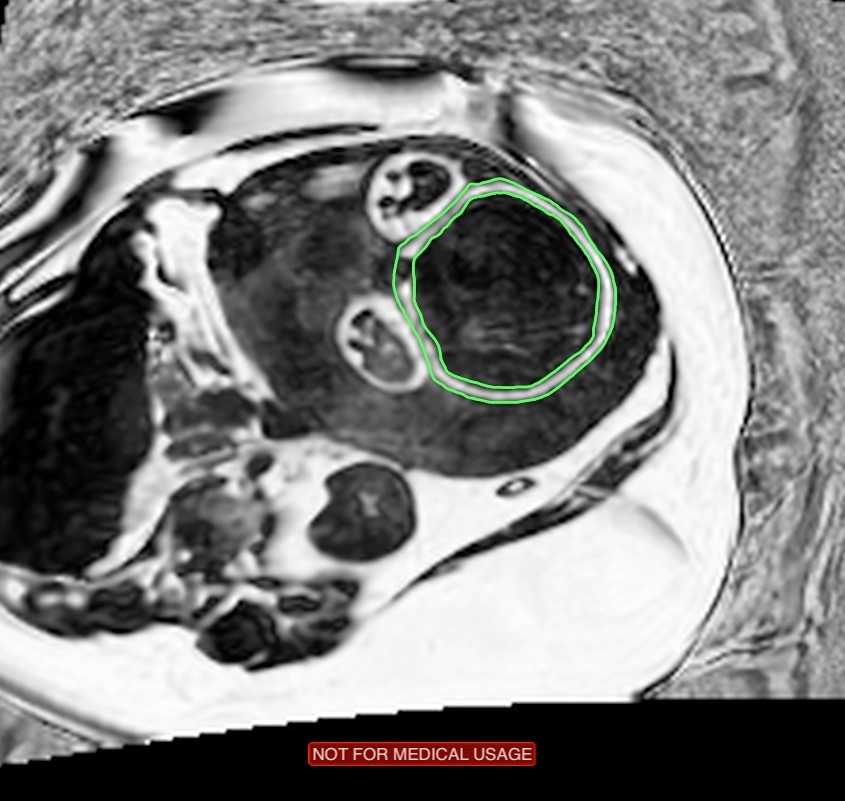

The goal of this project is to develop MRI methods to assess fetal metabolic status. State-of-the art MRI technologies will be employed, including BOLD MRI [5] to measure fetal and placental oxygenation, and water-fat MRI [6,7] to assess fetal adipose tissue distribution. Fetal subcutaneous fat is outlined in green on a fat signal fraction (fat/(water+fat)) image.